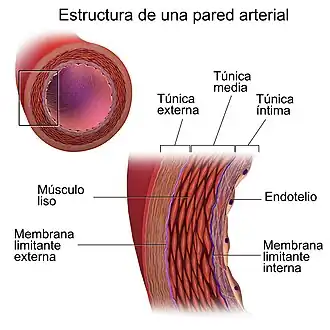

Histología

La pared de la aorta está formada por tres capas concéntricas: íntima, media y adventicia. La íntima se encuentra en contacto directo con la sangre y está formada por células endoteliales. La media es mucho más gruesa, está formada por hasta 50 capas concéntricas de láminas de elastina entre las que se intercalan células de músculo liso con capacidad contráctil. La adventicia es la capa más externa, es relativamente fina y está formada por fibroblastos, fibras de colágeno y elásticas.[11]